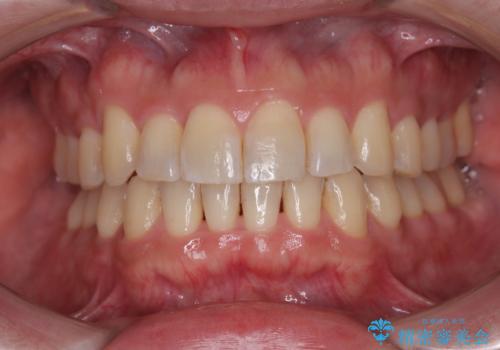

[ 矯正治療 ] 噛み合わせ前歯の見た目をきれいにしたい

![[ 矯正治療 ] 噛み合わせ前歯の見た目をきれいにしたいの症例 治療後](https://seimitsushinbi.jp/wp/wp-content/uploads/2025/08/IMG_3482-500x350.jpg?v=1754654765)